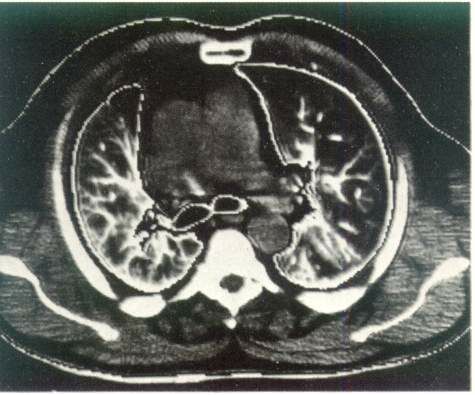

озможности рентгенологической диагностики заметно расширились за счет становления и клинического использования компьютерной рентгенотомографии. По сравнению с обычной рентгенографией компьютерная рентгенография имеет в десятки раз большую разрешающую способность и позволяет различать ткани с разностью по плотности до 0,5 %. Это дает возможность четко определять границу между нормальной и патологически измененной легочной тканью. На компьютерных томограммах органов грудной полости удается не только локализовать патологический очаг, но и определить его размеры, оценить плотность и однородность, соотношение с соседними анатомическими образованиями и органами.

Рис. 3. Компьютерная томография органов грудной клетки. Норма.

Компьютерная томография дает возможность получить наиболее полную рентгенологическую информацию об опухолях и кистах средостения, сосудистых изменениях в легких, аневризмах, о состоянии трахеобронхиального дерева, характере и структуре «шаровидных образований в легких», патологических изменениях в плевре, грудной стенке, особенно при ее злокачественных поражениях (рис. 3).